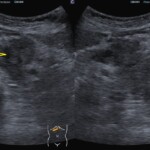

@腹部エコーで見つかった膵臓がん